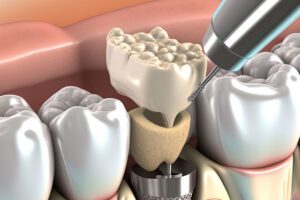

A dental implant in Fort Lauderdale, FL, is a prosthetic dental device surgically placed into the jawbone to replace a missing tooth. It consists of

Dealing with one or more missing teeth? For those who have missing teeth, they should consider getting treated with dental implants in Fort Lauderdale, FL.